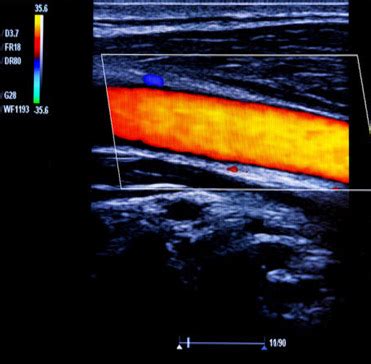

Alright, let’s get to the nitty-gritty of what Doppler ultrasound actually is. At its core, it’s a non-invasive medical imaging technique that uses sound waves to create images of blood flow inside your body. Think of it like a super-powered sonar for your veins and arteries! It’s a variation of the standard ultrasound we often associate with pregnancy scans, but with a special twist. The ‘Doppler’ part refers to the Doppler effect, a phenomenon that describes the change in frequency of a wave (in this case, sound waves) when the source of the wave and the observer are moving relative to each other. In medical terms, this means the ultrasound machine sends sound waves into your body, and when these waves bounce off moving red blood cells, their frequency changes. The ultrasound machine then detects this change in frequency, which allows it to measure the speed and direction of blood flow. Pretty cool, right? This ability to visualize and quantify blood flow is what makes Doppler ultrasound indispensable for diagnosing conditions like DVT, where the problem isn’t just the presence of a clot, but how that clot is affecting the normal circulation of blood.

Now, let’s talk about the star of the show: how Doppler ultrasound specifically helps us spot Deep Vein Thrombosis (DVT). DVT occurs when a blood clot, usually in a deep vein of the legs, blocks blood flow. This is serious business, as the clot can break off and travel to the lungs, causing a pulmonary embolism (PE), which is a life-threatening condition. Doppler ultrasound is the gold standard for diagnosing DVT because it can directly visualize these clots and, crucially, assess the impact on blood flow. The procedure typically involves a trained sonographer applying a gel to your skin over the suspected area (usually the legs) and then moving a transducer, a handheld device, over the skin. This transducer emits high-frequency sound waves. As these waves travel through your body, they bounce off various tissues and structures, including your blood vessels and the red blood cells within them. The machine listens to the returning echoes. In areas without a clot, the sound waves will reflect off the moving blood cells predictably, showing a normal flow pattern. However, when a clot is present, it can partially or completely block the vein. This blockage will alter the sound wave reflections in several ways:

1. Direct Visualization of the Clot: In many cases, the clot itself can be seen as an echogenic (bright) material within the vein, obstructing the normal lumen (the open space where blood flows). The sonographer looks for a lack of compressibility of the vein; a healthy vein will flatten when gentle pressure is applied by the transducer, but a vein filled with a clot will remain rounded.

2. Altered Blood Flow Patterns: This is where the ‘Doppler’ part really shines. The machine detects changes in the frequency of the returning sound waves. If blood flow is reduced or absent in a segment of the vein due to a clot, the Doppler signals will be weaker or absent altogether. The sonographer will assess ‘phasicity’ (the normal rhythmic changes in blood flow related to breathing) and ‘compressibility’ of the veins. A clot disrupts these normal flow characteristics.

3. Augmentation and Reflux: The sonographer may also perform maneuvers like squeezing the calf muscle below the area of interest. Normally, this would cause a surge of blood flow towards the heart (augmentation). If a clot is present, this surge might be diminished or absent. They also look for ‘reflux,’ which is when blood flows backward in the vein after a period of compression, indicating faulty valves often associated with chronic venous issues or significant DVT.

By combining these findings—visualizing the clot, assessing compressibility, and analyzing the Doppler signals for flow abnormalities—doctors can confidently diagnose DVT. It’s a powerful tool because it provides real-time information about the health of your venous system, helping to guide treatment decisions and prevent serious complications.